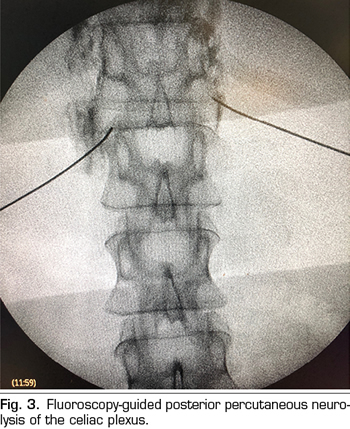

Figure 3